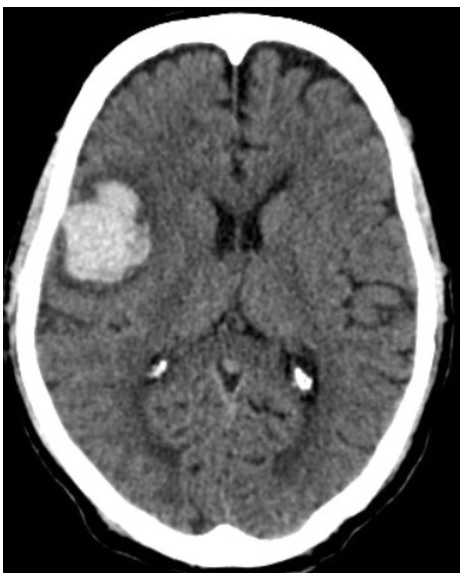

Οι συνηθισμένες θέσεις αιμορραγίας είναι τα βασικά γάγγλια (50%), οι λοβοί του εγκεφάλου (10% - 20%), ο θάλαμος (15%), η γέφυρα και το εγκεφαλικό στέλεχος (10% - 20%), και η παρεγκεφαλίδα (10%) (φωτ.1,2,3)[1]

Fig.02. CT scan of lobar hemorrhage. Owned by Dr. Ajaya Kumar A.